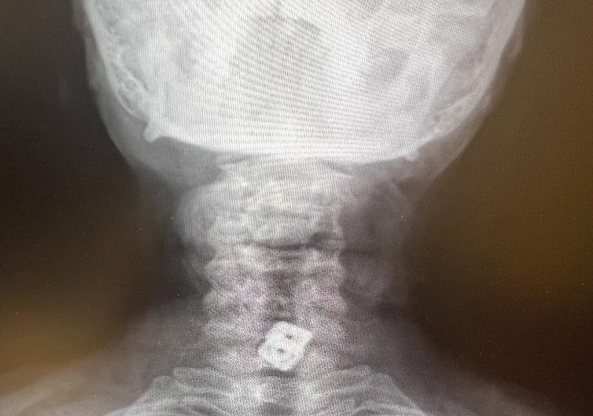

Kahramanmaraş'ta yaşayan ev hanımı Sultan Tıraş (40), sekiz ay önce kolunun sık sık uyuşması nedeniyle bir sağlık kuruluşuna başvurduğunda, boyun fıtığı teşhisi konulduğu ve yapılan ameliyatla boyun omurlarına metal disk yerleştirildi. Operasyon sonrası iyileşen ancak ameliyattan iki ay sonra gırtlağında batmalar hisseden kadının ağrıları her geçen gün daha da arttı. Tekrar hastaneye başvuran kadına, sürecin normal olduğu ve şiddetli bir ağrısı yoksa normal yaşantısına devam edebileceği söylendi. Şubat ayında yaşanan deprem felaketi sonrası Bursa’ya giden kadın, burada başvurduğu hastanede, boyun omuruna takılan metal diskin gırtlağını delme ihtimali olduğunu öğrendi. Büyük şok yaşayan kadın, Kahramanmaraş’a döndüğünde acilen ameliyat olması gerektiğini öğrendi.

SANKO Üniversitesi Tıp Fakültesi Göğüs Cerrahisi Ana Bilim Dalı Başkanı Prof. Dr. Elbeyli, bilinci kapalı olarak hastaneye getirilen Sultan Tıraş’ın, ciddi ve hayatını kaybetme riski çok yüksek bir olay yaşadığını vurguladı. Sultan Tıraş’ın Gaziantep’te başka özel hastanede yapılan radyolojik tetkikler ve değerlendirmeler sonucu daha önce başka bir merkezde boyun omurlarına yerleştirilen metal disklerin yerinden oynadığının belirlendiğini hatırlatan Prof. Dr. Elbeyli, sözlerini şöyle sürdürdü: “O hastanede beyin ve sinir cerrahisi uzmanı tarafından ameliyata alınan Sultan Tıraş’ın boyun omuruna konulan iki aparattan biri çıkarılmış, ancak diğerinin yemek borusunu delip mideye indiği belirlenmiş. İlgili hekim bana ulaşarak bilgilendirmeyi yaptı ve hastayı hastanemize sevk etti. Yoğun bakıma alınan hastaya yaptığımız detaylı tetkikler ve klinik değerlendirme sonucu mediyastenit (ciddi göğüs enfeksiyonu) belirlendi. Bu ciddi bir sorun olup, hayati riski yüksektir. En hızlı şekilde tıbbi tedaviye başladık, gastroenteroloji bölümümüzde endoskopi yapıldı. Yemek borusunda oluşan delik ve delikten mideye inen metalik cerrahi aparat görüldü. Göğüs kafesi içinde ciddi bir iltihap ve hava birikimi vardı. Hasta yakınları durum ile ilgili bilgilendirildi, riskler kendileri ile paylaşılarak hastamıza tıbbi müdahale edebilmemiz gerekli onayları alındı.”